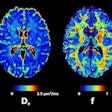

Hyperfine launches MRI brain study